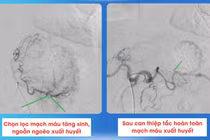

Bệnh nhân được tiến hành phẫu thuật theo phương án: gỡ dính và sắp xếp lại các quai ruột theo đúng giải phẫu; cắt 3/4 dạ dày và nạo vét hạch D2 - phẫu thuật triệt căn trong ung thư dạ dày; cắt ruột thừa để phòng ngừa nguy cơ viêm ruột thừa sau này do nằm sai vị trí.

ThS.BSCKII Trần Minh Phương, Giám đốc Trung tâm Y tế Việt Yên, người trực tiếp phẫu thuật cho biết: "Đây là ca mổ tương đối khó vì có cả tổn thương ung thư và dị dạng bẩm sinh. Việc phẫu thuật không chỉ cần loại bỏ triệt để khối u mà còn phải sắp xếp lại hệ tiêu hóa để tránh biến chứng sau mổ. Nếu không phát hiện và xử trí kịp thời, cả hai bệnh lý đều có thể diễn tiến nặng, gây nguy hiểm tính mạng".